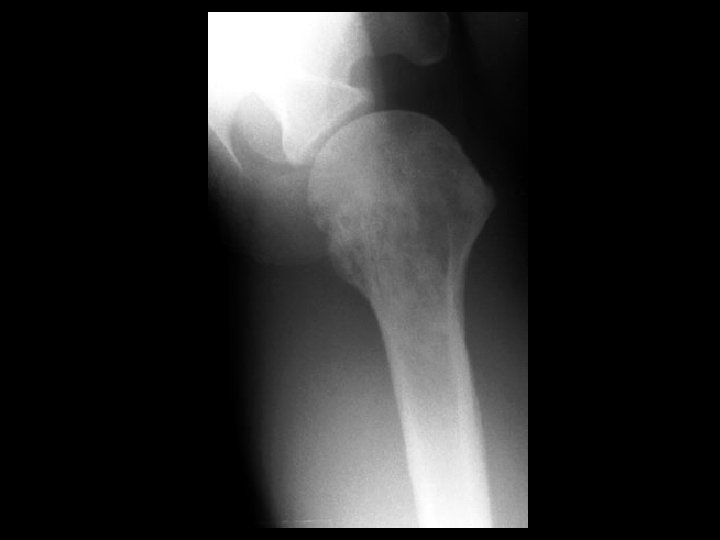

Fibrous dysplasia • Findings: – Mixed sclerotic and lytic lesion of the left hemipelvis and proximal femur – “shepherd's crook sign” • ddx: – NONE! – This is an Aunt Minnie!